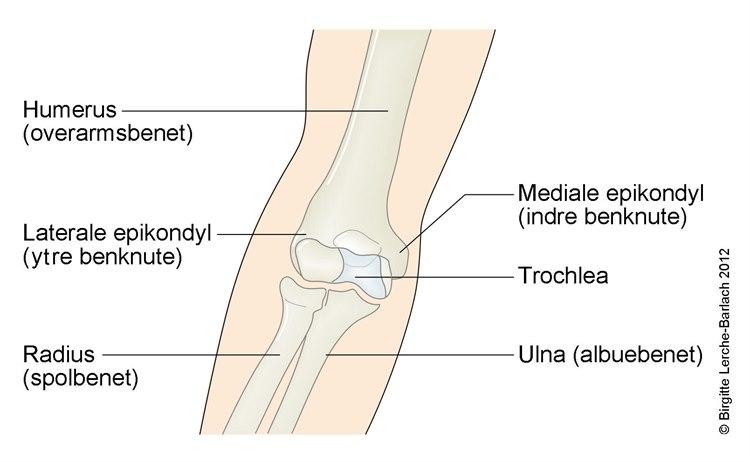

- Tennisalbue (lateral epikondylitt)

- Er den vanligste årsak til albuesmerter. Det foreligger en betennelse i et senefeste på yttersiden av albuen som skyldes akutt eller langvarig overbelastning

- Tilstanden gir moderate smerter som forverres ved bruk av hånden. Det er lokal ømhet når du trykker mot beinet på utsiden i albuen

- Golfalbue (medial epikondylitt)

- Er mindre vanlig enn tennisalbue. Det foreligger en betennelse i et senefeste på innsiden av albuen som skyldes overbelastning

- Tilstanden gir moderate smerter på innsiden av albuen som forverres ved bruk av hånden